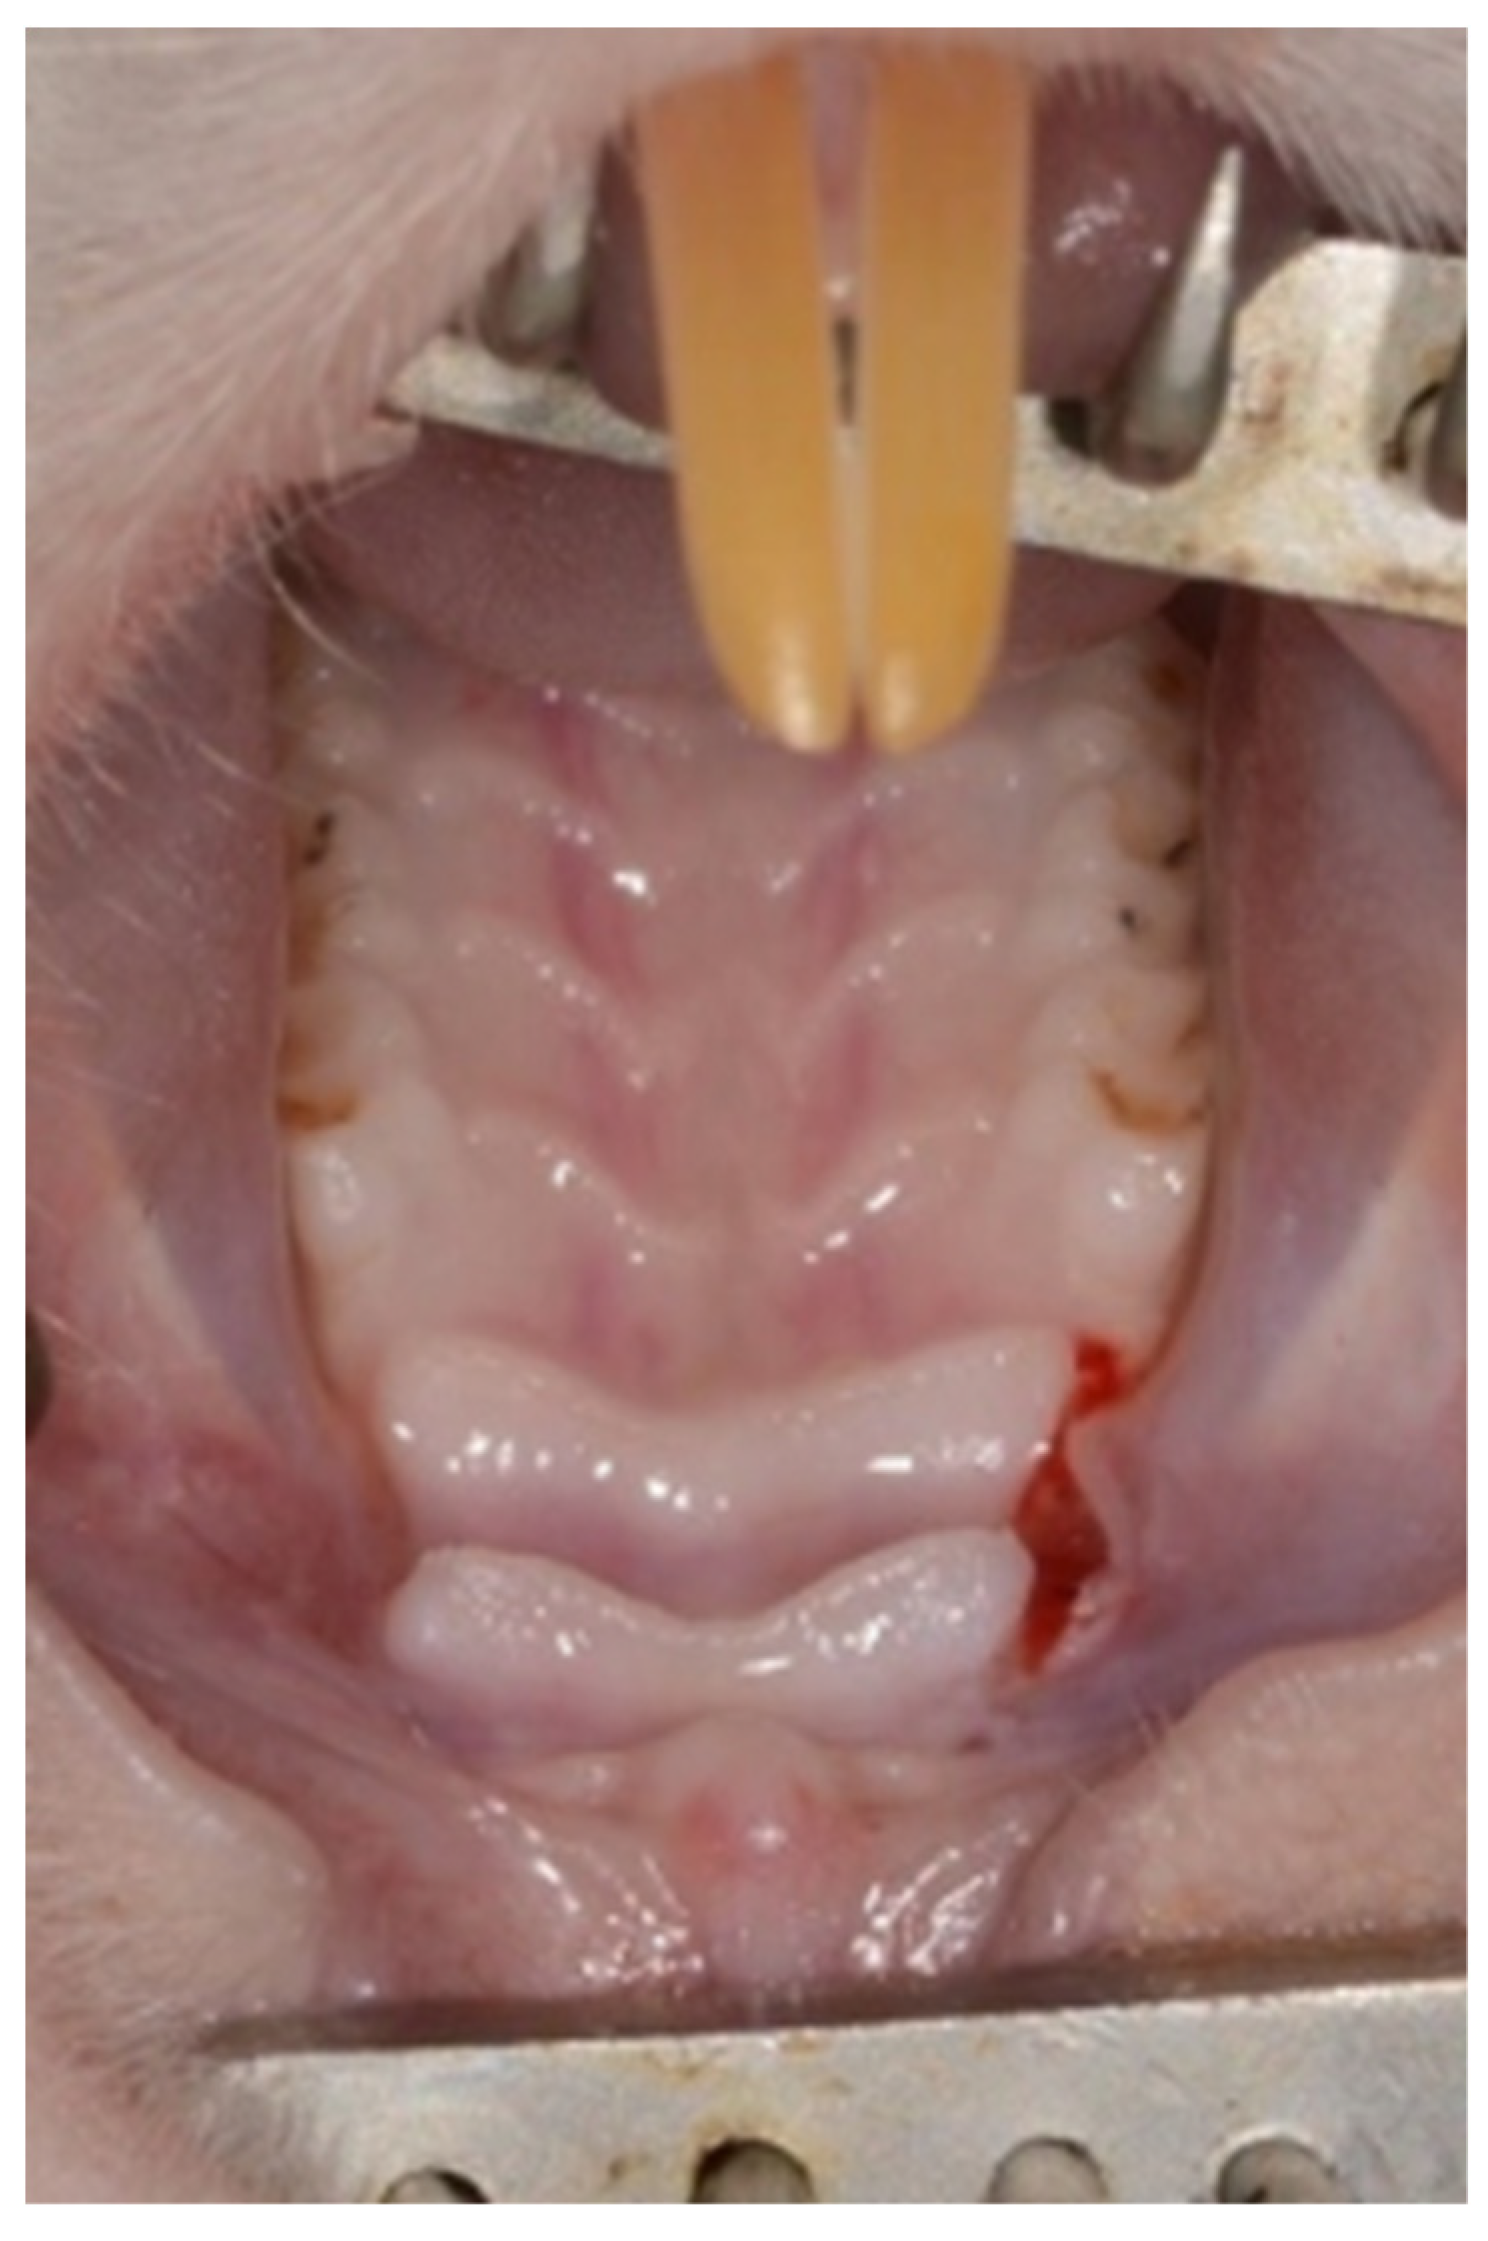

A full thickness flap was raised bilaterally and was then repositioned and sutured with resorbable Vicryl RapidTM 5-0 sutures (Ethicon Inc., Johnson & Johnson, NJ, USA) (Figure 2).

Figure 2. Primary closure with resorbable sutures.